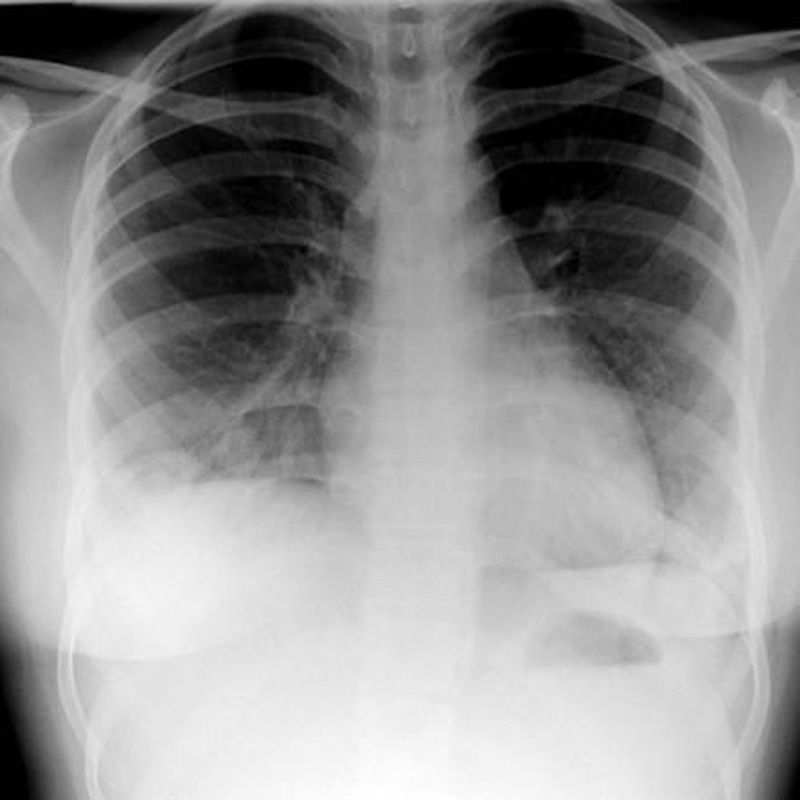

Pulmonary Wegener's granulomatosis can present with multifocal lung involvement or solitary lung lesions with no evidence of extrapulmonary disease